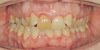

Das Quietschen fällt mir schon gar nicht mehr auf. Aber ich trage sie weiterhin fleißig. Ich kann schon sagen, dass sich der Zahn, gut eingestellt hat. Vor vier Monaten konnte ich noch die Kaufläche mit meiner Zunge beim zubeißen erfühlen. Das geht jetzt nicht mehr. Ich schaue mal, ob ich gleich noch die Fotos meiner KFO vor der Behandlung und von vier Wochen hochladen kann. Da kann man den Unterschied schon gut erkennen. Was ich als Laie halt so sagen kann. Außerdem habe ich das Gefühl, dass mein rechter vorderer Eckzahn etwas mehr Platz hat und nicht mehr so weit nach vorne steht.

Okklusion_rechts-Anfangsdiagnostik-2023_09_20-0_2[1].jpg Okklusion_Anterior-Anfangsdiagnostik-2023_09_20-0_1[2].jpg Okklusion_links-Anfangsdiagnostik-2023_09_20-0_3[1].jpg Okklusion_OK-Anfangsdiagnostik-2023_09_20-0_4[1].jpg Okklusion_UK-Anfangsdiagnostik-2023_09_20-0_5[1].jpg DSC_7646[1].JPG DSC_7649[1].JPG DSC_7651[1].JPG DSC_7652[1].JPG DSC_7655[1].JPG

Ich hoffe, ihr könnt auf diesen Bildern die Entwicklung sehen.